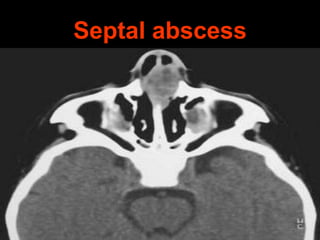

Septal abscess

Collection of pus under perichondrium

& periosteum of nasal septum.

Aetiology:

1. secondary infection of septal hematoma

2. following furuncle of nose or upper lip

3. following typhoid or measles

Clinical Features

• Bilateral nasal obstruction with fever

• Skin over nose shows raised

temperature, erythema, swelling & tenderness

• B/L smooth, soft, fluctuant septal swelling

• Septal mucosa congested

• Submandibular node enlarged & tender

Treatment

• Abscess drained immediately

• Incision made on most dependent part

• Pus & necrosed cartilage removed

• Nasal packing done

• Systemic antibiotics for 10 days

Complications

• Necrosis of septal cartilage

• Saddle nose

• Supra-tip deformity

• Septal perforation

• Meningitis

• Cavernous sinus thrombosis